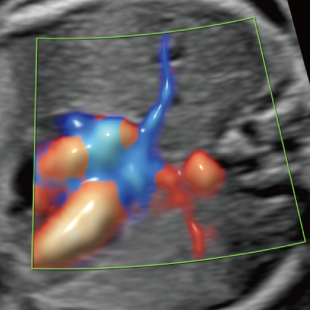

赤ちゃんの3~5%は、何らかの病気や医学的な介入を要する状態をもって生まれてくるといわれており、その中には、妊娠中・出生時・出生後に緊急の対応を要するものも含まれます。 特に先天性心疾患は比較的頻度が高く、約100人に1人の赤ちゃんが先天性心疾患を合併し、重症度や緊急性の高い症例(生後に入院や手術が必要な症例)は約1000人に4人といわれています。

Voluson Expert 22®(GEHealthcare)という産婦人科領域におけるハイエンド超音波診断装置を使用しています。 従来機種と比べ、より高精細な画像描出性能と高度な解析機能を備えており、 胎児の発育や形態をより詳細に観察することが可能です。